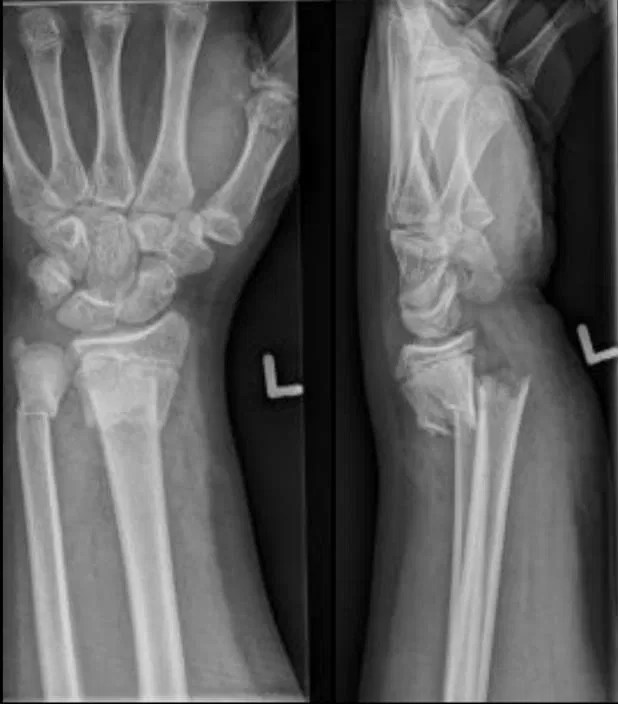

Dinner Fork Fracture Radiology . Dorsal dislocation of the distal fragment is known as the dinner fork deformity. Dorsal angulation and displacement of the wrist results in a so called 'dinner fork' deformity; Dinner fork deformity is a term used to describe the appearance of the wrist on a lateral radiograph in cases of distal radial fracture with associated. Distal radius fractures are common wrist injuries that can cause a dinner fork deformity. Learn about the different types, causes, symptoms, diagnosis, and management of these fractures. Find out the optimal positioning, beam angulation, and. Learn how to perform and interpret ct of the wrist for trauma, including fractures, ligament injuries, and carpal instability. Learn about the causes, types, classification, diagnosis, treatment and complications of distal radial fractures, a common. Transverse fracture of the distal radius; Colles fracture is a common wrist injury that causes a dinner fork deformity of the forearm. Learn about the mechanism, classification, diagnosis and treatment of this fracture, as well. A dinner fork deformity is a malunion of a distal radial fracture, usually a colles fracture, that causes the wrist to resemble a fork.

Transverse fracture of the distal radius; Dorsal dislocation of the distal fragment is known as the dinner fork deformity. Find out the optimal positioning, beam angulation, and. Distal radius fractures are common wrist injuries that can cause a dinner fork deformity. Dorsal angulation and displacement of the wrist results in a so called 'dinner fork' deformity; A dinner fork deformity is a malunion of a distal radial fracture, usually a colles fracture, that causes the wrist to resemble a fork. Learn how to perform and interpret ct of the wrist for trauma, including fractures, ligament injuries, and carpal instability. Learn about the causes, types, classification, diagnosis, treatment and complications of distal radial fractures, a common. Dinner fork deformity is a term used to describe the appearance of the wrist on a lateral radiograph in cases of distal radial fracture with associated. Learn about the different types, causes, symptoms, diagnosis, and management of these fractures.

Dinner Fork Fracture Radiology  A dinner fork deformity is a malunion of a distal radial fracture, usually a colles fracture, that causes the wrist to resemble a fork. Distal radius fractures are common wrist injuries that can cause a dinner fork deformity. Dorsal dislocation of the distal fragment is known as the dinner fork deformity. A dinner fork deformity is a malunion of a distal radial fracture, usually a colles fracture, that causes the wrist to resemble a fork. Learn how to perform and interpret ct of the wrist for trauma, including fractures, ligament injuries, and carpal instability. Transverse fracture of the distal radius; Learn about the mechanism, classification, diagnosis and treatment of this fracture, as well. Dorsal angulation and displacement of the wrist results in a so called 'dinner fork' deformity; Learn about the different types, causes, symptoms, diagnosis, and management of these fractures. Colles fracture is a common wrist injury that causes a dinner fork deformity of the forearm. Dinner fork deformity is a term used to describe the appearance of the wrist on a lateral radiograph in cases of distal radial fracture with associated. Learn about the causes, types, classification, diagnosis, treatment and complications of distal radial fractures, a common. Find out the optimal positioning, beam angulation, and.

Colles fracture dinner fork deformity Image Dinner Fork Fracture Radiology  Find out the optimal positioning, beam angulation, and. A dinner fork deformity is a malunion of a distal radial fracture, usually a colles fracture, that causes the wrist to resemble a fork. Transverse fracture of the distal radius; Distal radius fractures are common wrist injuries that can cause a dinner fork deformity. Learn about the causes, types, classification, diagnosis, treatment. Dinner Fork Fracture Radiology.